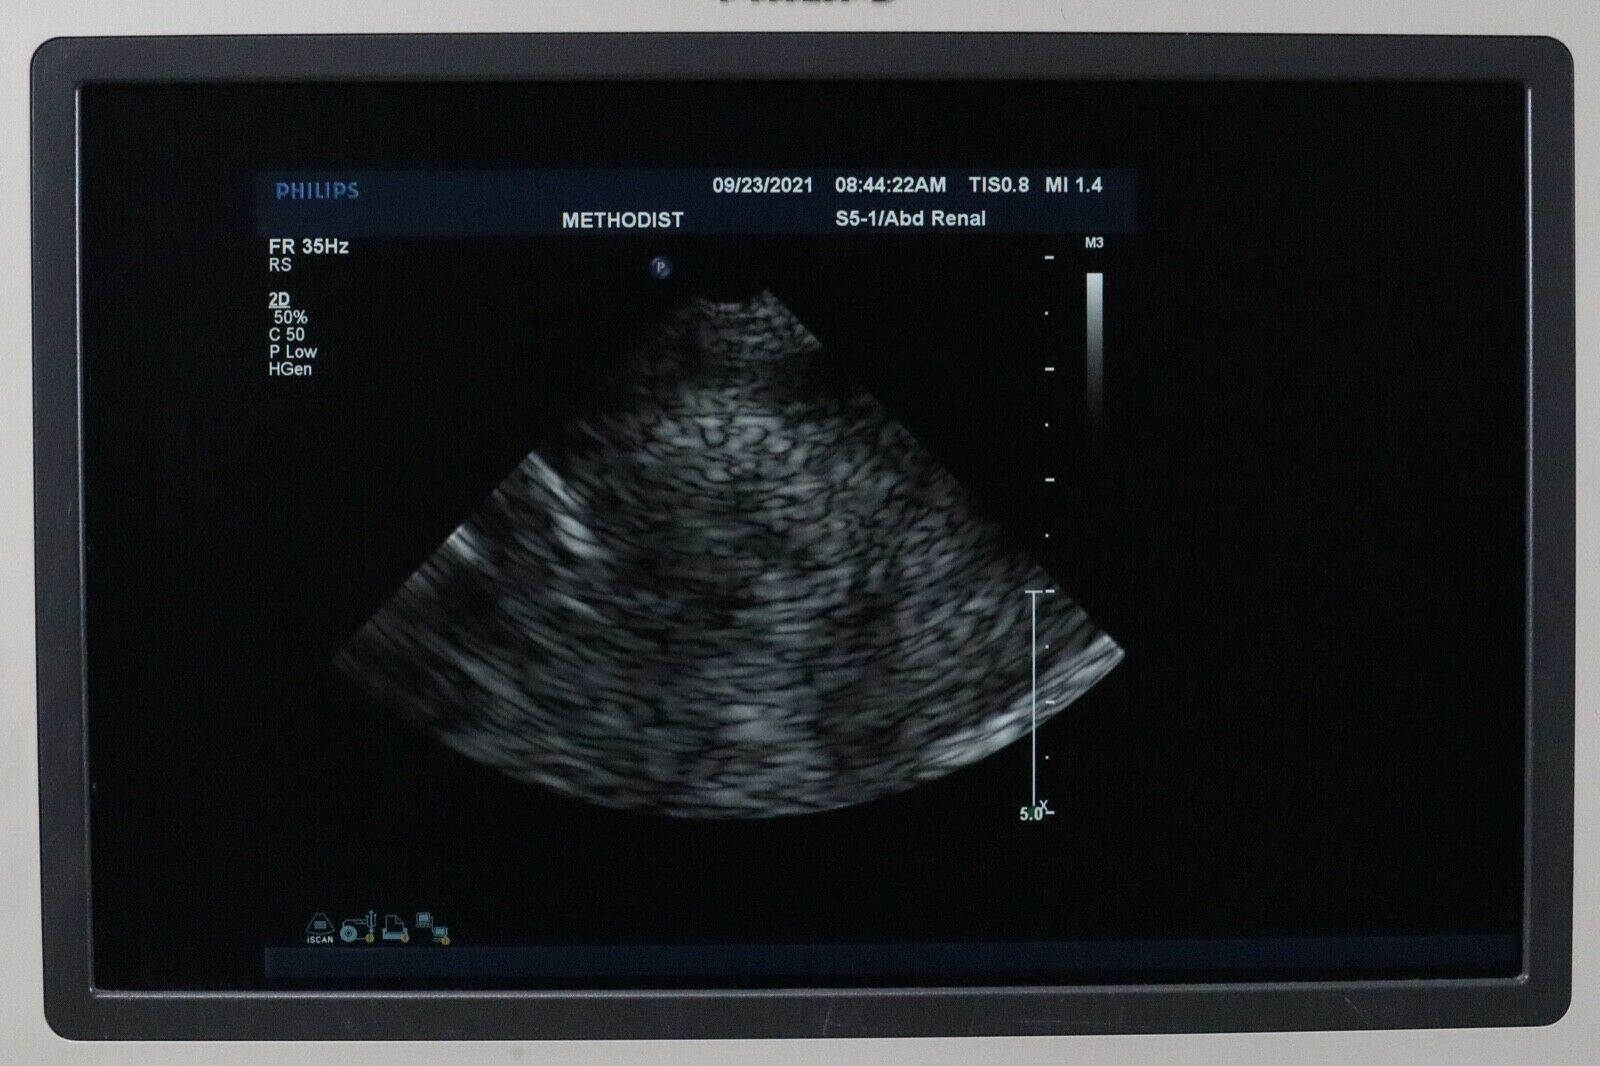

PHILIPS S5-1 SECTOR ARRAY ULTRASOUND PROBE

The Philips S5-1 Sector Array Ultrasound Probe is a high-performance imaging transducer designed for a range of clinical applications, including abdominal, cardiac, and obstetric/gynecological imaging. With a frequency range of 1-5 MHz, this probe offers excellent tissue penetration for deeper imaging, while maintaining high-resolution images for accurate diagnostics. The sector array design enables the probe to capture detailed images from a small footprint, making it ideal for patients with challenging body types or when accessing confined anatomical areas.

The Philips S5-1 probe is widely used for echocardiograms and other cardiovascular applications, as well as abdominal and obstetric exams. Known for its durability and reliability, it is compatible with Philips ultrasound systems and supports a variety of imaging modalities such as Doppler and 2D imaging. The S5-1 is designed for ease of use, providing clinicians with clear, real-time images to guide accurate diagnoses and treatment decisions.